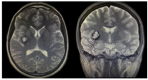

Vascular malformations are frequent in the head and neck region, affecting the nervous system. The wide range of therapeutic approaches demand the correct anatomical, morphological, and functional characterization of these lesions supported by imaging. Using a systematic search protocol in PubMed, Google Scholar, Ebsco, Redalyc, and SciELO, the authors extracted clinical studies, review articles, book chapters, and case reports that provided information about vascular cerebral malformations, in accordance with Preferred Reporting Items for Systematic Reviews and Meta-Analyses (PRISMA) guidelines. A total of 385,614 articles were grouped; using the inclusion and exclusion criteria, three of the authors independently selected 51 articles about five vascular cerebral malformations: venous malformation, brain capillary telangiectasia, brain cavernous angiomas, arteriovenous malformation, and leptomeningeal angiomatosis as part of Sturge-Weber syndrome. We described the next topics-"definition", "etiology", "pathophysiology", and "treatment"-with a focus on the relationship with the imaging approach. We concluded that the correct anatomical, morphological, and functional characterization of cerebral vascular malformations by means of various imaging studies is highly relevant in determining the therapeutic approach, and that new lines of therapeutic approaches continue to depend on the imaging evaluation of these lesions.